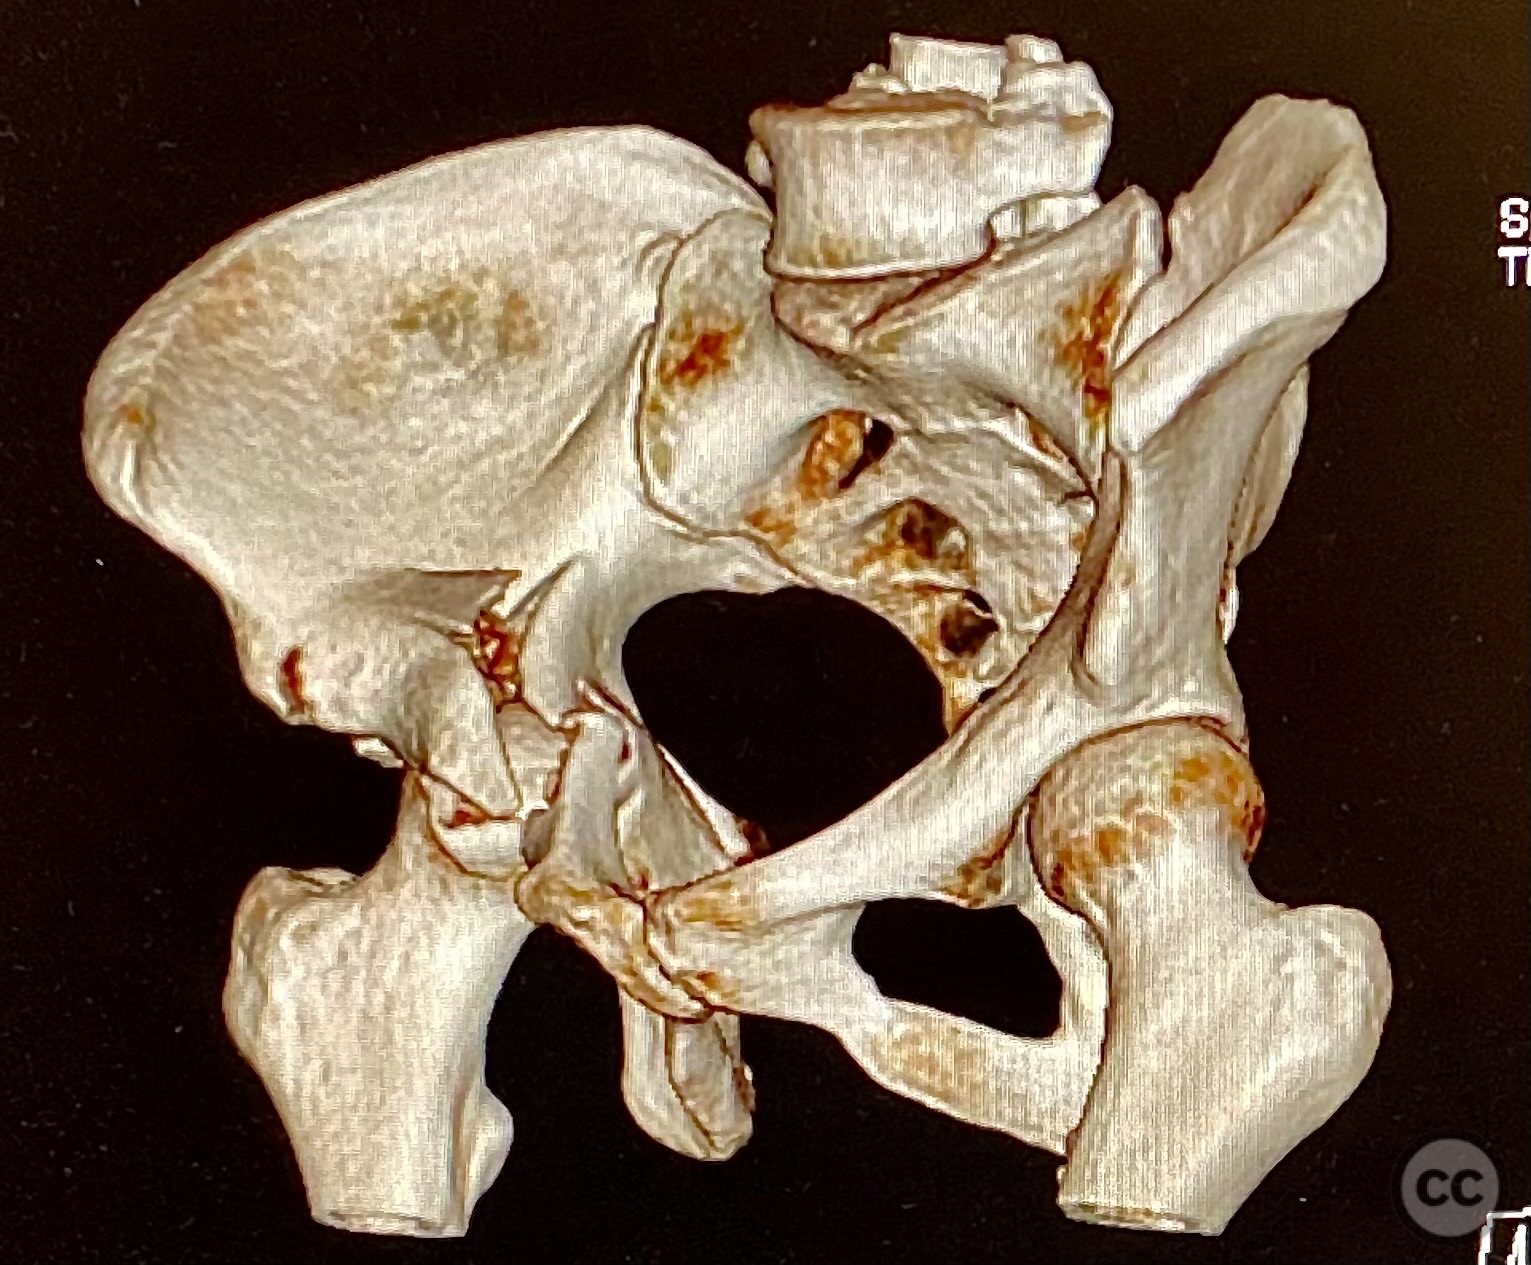

Clinical and radiological findings:  The patient sustained an acetabular fracture with a rare posterior medial dome impaction fragment, as demonstrated on AP pelvic radiographs obtained in skeletal traction. Surface renderings and axial CT images revealed multiple incomplete fracture lines, including a rhomboid-shaped cortical fragment adjacent and proximal to the anterior column/wall fragment. Coronal and sagittal reconstructions further delineated the impacted articular fragment and its relationship to the surrounding acetabular dome. The fracture pattern is classified as AO/OTA 62B3 (associated both-column fracture with dome impaction).